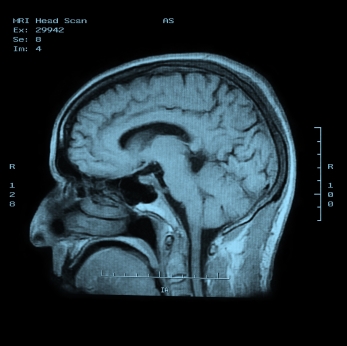

Менингит (воспаление мозга позвоночника) фото

Врач осматривает больного, изучает анамнез, жалобы и клиническую картину заболевания. Проводит физикальный осмотр. Для диагностики и дифференциальной диагностики менингита необходимо, прежде всего, исследовать ликвор (спинномозговую жидкость) для идентификации возбудителя. Также берут мазок из носа для выявления менингококков при носительстве. Лабораторные и инструментальные исследования: рентгенография черепа, КТ,МРТ, исследование ликвора, клинический и биохимический анализы крови, анализ мочи.

Медицинские процедуры, проводимые при заболевании менингит: Мазок из носа на микрофлору, Спинальная пункция, Биохимический анализ ликвора, Бактериологическое исследование, Микроскопические исследования, Посев исследуемого материала на питательные среды, ПЦР-диагностика, Спиральная компьютерная томография, Магнитно-резонансная томография, Рентгенография черепа, Биохимический анализ крови, Клинический анализ крови, Анализ мочи